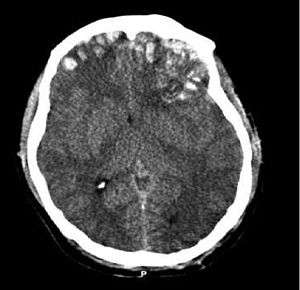

| CT scan showing cerebral contusions, hemorrhage within the hemispheres, subdural hematoma, and skull fractures[1] | |

Systems also exist to classify TBI by its pathological features.[12] Lesions can be extra-axial, (occurring within the skull but outside of the brain) or intra-axial (occurring within the brain tissue).[17] Damage from TBI can be focal or diffuse, confined to specific areas or distributed in a more general manner, respectively.[18] However, it is common for both types of injury to exist in a given case.[18]

One type of focal injury, cerebral laceration, occurs when the tissue is cut or torn.[30] Such tearing is common in orbitofrontal cortex in particular, because of bony protrusions on the interior skull ridge above the eyes.[24] In a similar injury, cerebral contusion (bruising of brain tissue), blood is mixed among tissue.[15] In contrast, intracranial hemorrhage involves bleeding that is not mixed with tissue.[30]

Hematomas, also focal lesions, are collections of blood in or around the brain that can result from hemorrhage.[3] Intracerebral hemorrhage, with bleeding in the brain tissue itself, is an intra-axial lesion. Extra-axial lesions include epidural hematoma, subdural hematoma, subarachnoid hemorrhage, and intraventricular hemorrhage.[31] Epidural hematoma involves bleeding into the area between the skull and the dura mater, the outermost of the three membranes surrounding the brain.[3] In subdural hematoma, bleeding occurs between the dura and the arachnoid mater.[15] Subarachnoid hemorrhage involves bleeding into the space between the arachnoid membrane and the pia mater.[15] Intraventricular hemorrhage occurs when there is bleeding in the ventricles.[31]